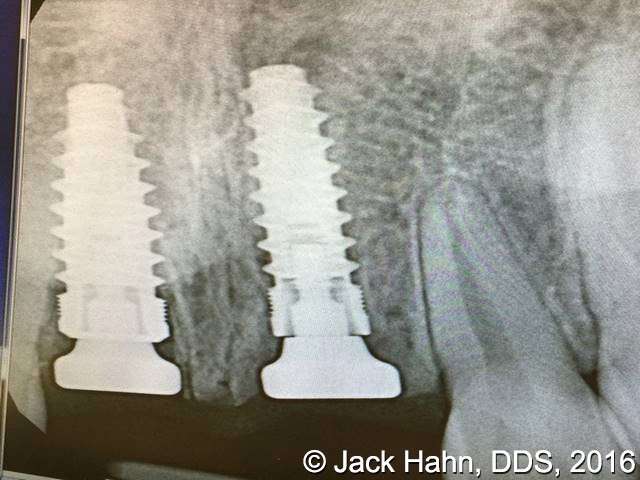

CASE #4 Trauma Case – Central Incisors Internal / External Resorption

Implants, that replace failed endo- or perio-compromised teeth, have a MUCH higher success rate with laser decontamination of the osteotomy site. LightScalpel laser surgical and perio laser tips ensure excellent access to extraction socket for the optimum removal of granulation tissue and socket decontamination (protocol involves manual curettage of the socket with alternating rinsing and lasing).

The patient, a 17-year-old female was involved in a water slide accident 3 years ago. As a result, both central incisors were avulsed and an endodontist replanted them. Both teeth exhibited internal and external resorption. Dr. Hahn extracted both central incisors, removed all the root fragments and sanitized the sites with the LightScalpel laser which also eliminated any granulation tissue. The #8 area was prepared to place a Hahn 4.3×13 Implant and #9 was prepared for a Hahn 3.5×13. 3mm tall Hahn healing abuts were placed slightly below the gingival-tissue level to help develop an emergence profile when at the restoration time in 4 months. Upon seeing the x-ray, Dr. Hahn tightened the healing abutment on #9 to be sure that it was completely seated on the implant. 45nucm. stability was achieved on both implants. He then placed some bone putty to seal any openings. To be on the safe side, he decided to place a temporary partial instead of immediate temporary prosthetics.